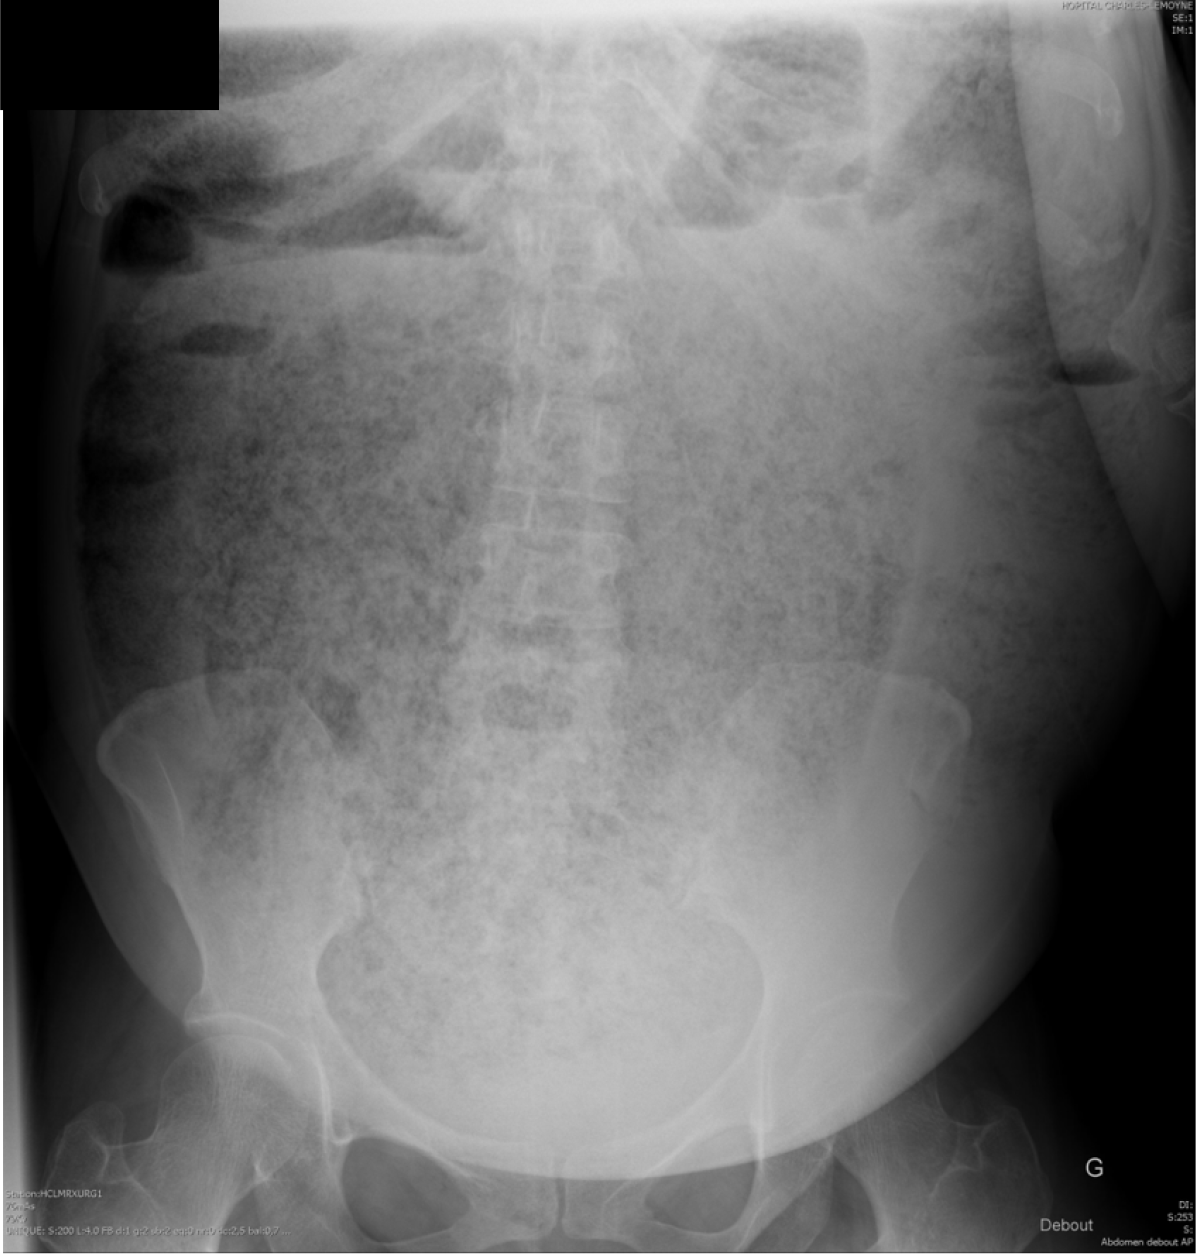

Figure 2 Abdominal computed tomography.

A: Coronal view showing diffuse colonic distension with accumulation of stools. The rectal wall is thickened (small arrows) and a large and dense fecaloma is demonstrated within the lumen (large arrow); B: Rectum with a dense 100-mm fecaloma (large arrow); C: Rectum reaching 193 mm in diameter.